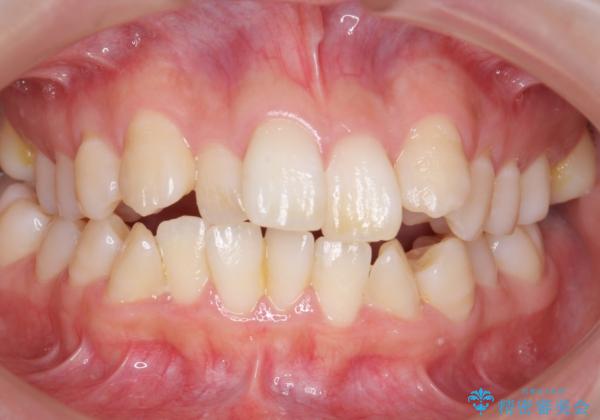

- 歯並びを気にして来院。

前歯は重度のがたつき、また奥歯はすれ違っていました。